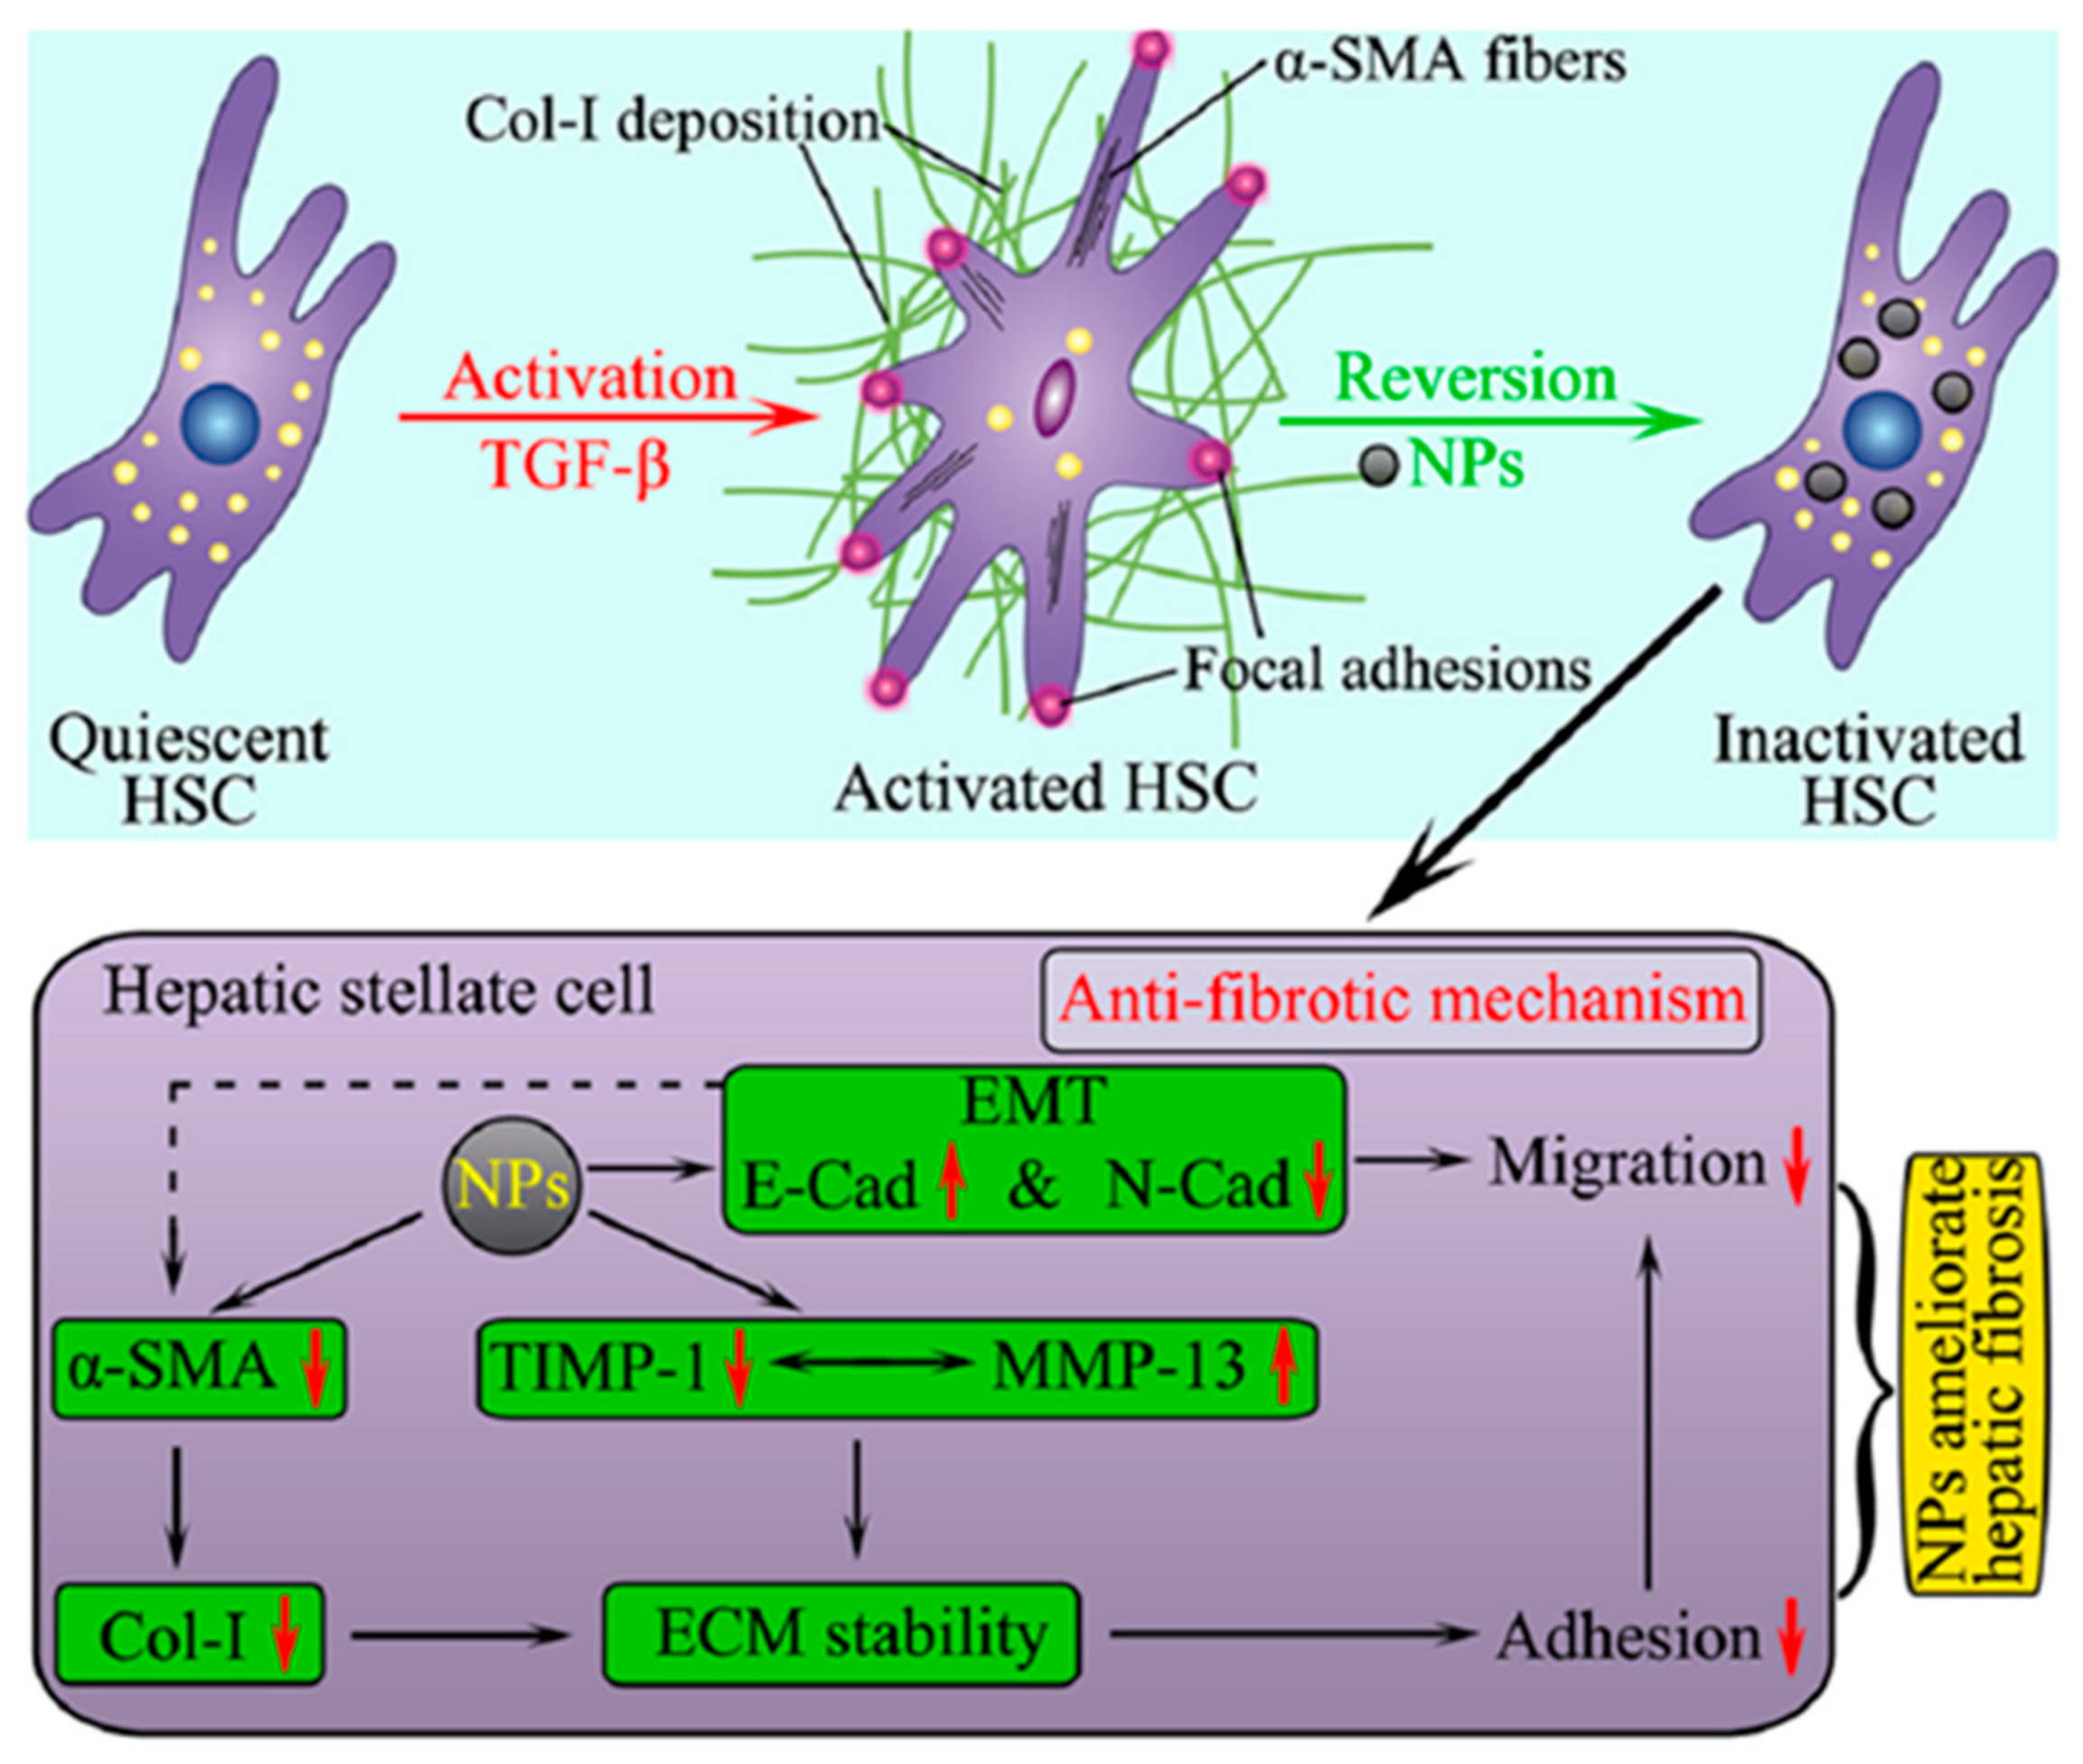

2.1. Targeting HSCs

4.1. NPs as Therapeutic Agents